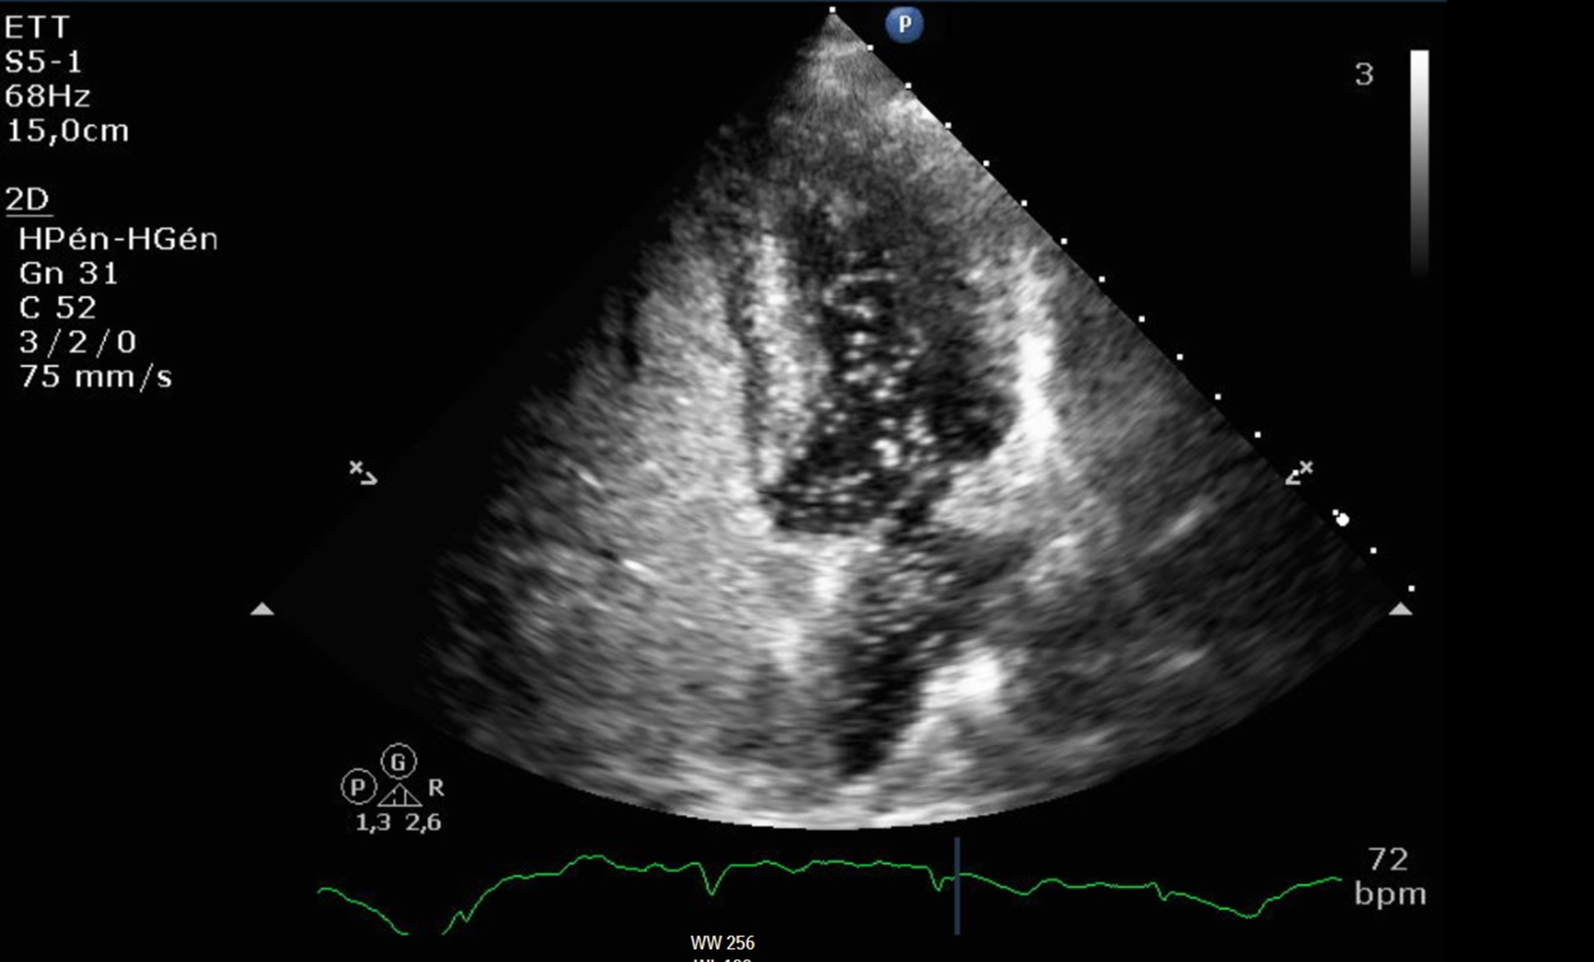

Fig. 3From: Patent foramen ovale revealed by COVID-19 pneumoniaBubble contrast echocardiography. Two-dimensional transthoracic echocardiography image showing a right-to-left shunt upon release of the Valsalva maneuverBack to article page